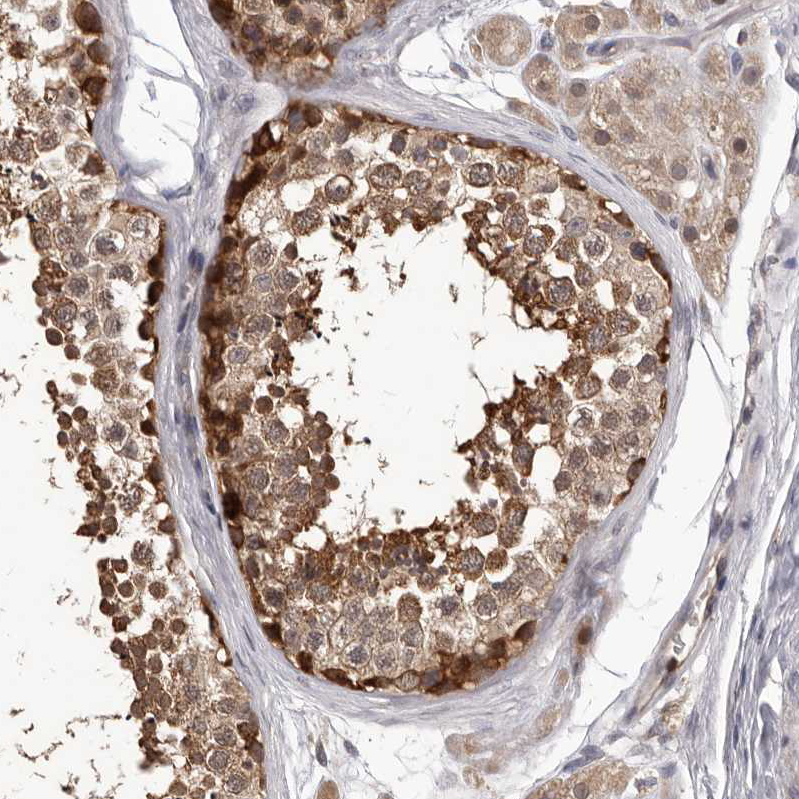

Immunohistochemical staining of human rectum shows strong cytoplasmic positivity in glandular cells.